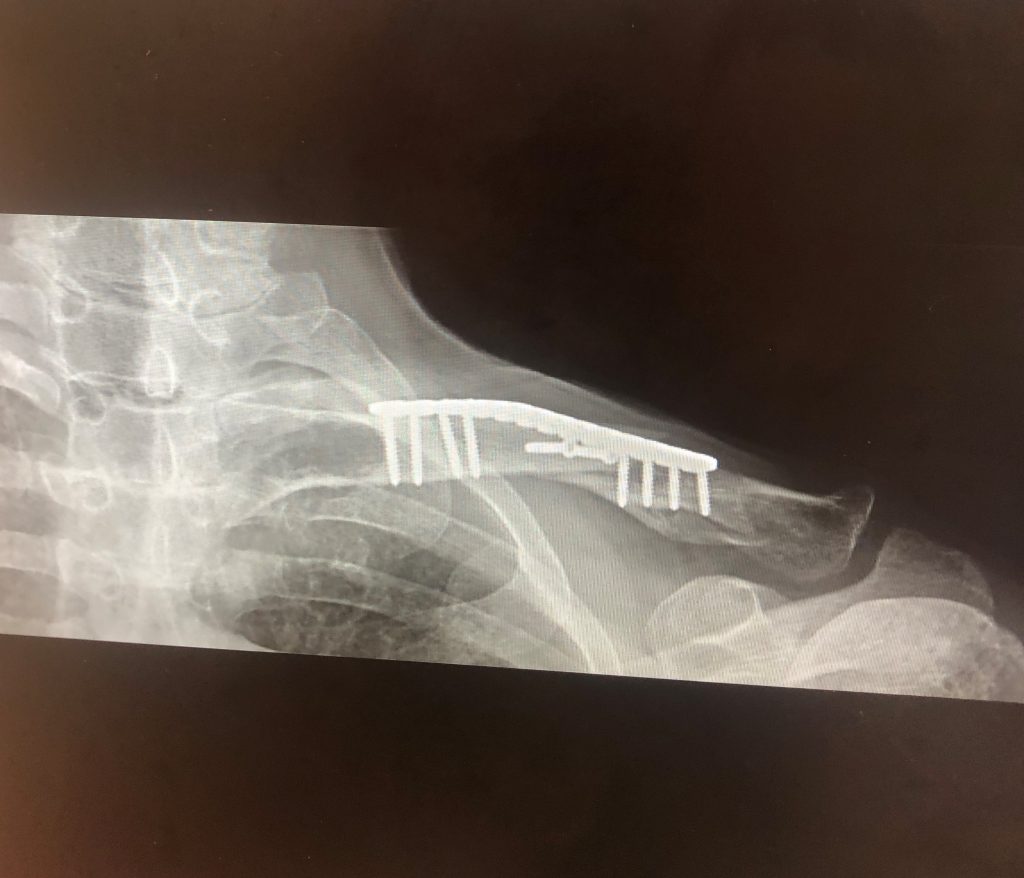

My second story is one that occurred more recently. In mid-August 2022, I was riding my bike to go teach a yoga class and a man in a parked car opened his door in front of me. I was thrown from my bicycle pretty violently. I looked down and saw my collarbone almost protruding through my skin. After the EMS took me to the nearest hospital and it was discovered that not only had my collarbone snapped and overlapped, but I also broke 3 ribs and had contusions in my hips from the blunt force of the fall. Because the x-rays showed the rib damage, I had to be transferred to a trauma facility, which, lucky for me, was HSS at NYP. It was there where I had the fortune of meeting Dr. Behrens, who immediately put my mind at rest and made me feel in vey safe hands.

He performed a procedure in which he reattached my collarbone with a metal plate and 10 screws. I was in the hospital for a few days, obviously, but once again I felt so taken care of and nurtured. I was more than pleasantly surprised at my speedy recovery. In such a short period of time, maybe in just two weeks, I was back teaching yoga and pretty soon after that, had full range of motion in my arms and shoulders and was back to my normal routine. Everyone around me was astounded at how quickly I had bounced back. I owe that all to Dr. Behrens. His work was immaculate and dare I say perfect. Once again, I have no more pain and am will be forever grateful that Dr Behrens was on the staff that day.